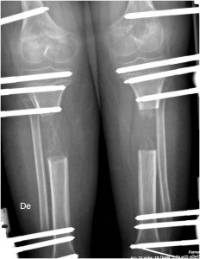

Dependiendo de la talla del paciente se realizará un alargamiento bilateral de femur o alargamiento bilateral de tibia.

La tibia es el hueso más propicio para hacer alargamientos pues tiene una forma tubular y parte de ella es superficial y accesible.

Por otro lado la pierna tiene un hueso adicional y pegado a la tibia por ligamentos, que es el peroné este hay que seccionarlo para que permita alargar la tibia. Es importante entender que la tibia es la que trasmite la carga de la extremidad y el peroné es un hueso accesorio para la carga y solo es importante en la parte proximal, donde se insertan los ligamentos de la rodilla y en la zona distal con los ligamentos de la sindesmosis, la zona articular de la tibia y el maleolo tibial forman la articulación del tobillo.

Siempre que respetemos estas dos estructuras el peroné se puede resecar sin ninguna consecuencia, pues la tibia no se puede alargar si no se corta el peroné.